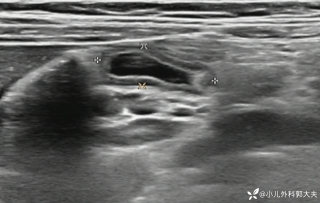

灼见|如果是你,如何处置山东男孩(多器官切除病例)

文/西地兰 特别声明:所有观点仅代表个人言论 特别声明:与当事双方均无利益相关 山东男孩,目前全网沸沸扬扬,看过一些观点,直言不讳地说,大多偏颇。要么一股脑地指责医方的全责,甚至有说千万别在县医院看病。要么又为医方无休止的遮羞,认为这样的手术在县医院做下来已经非常了不起。而我想到的是,以后面临类似的病例,我们怎么办?那么我们不如来一次专业的病案讨论。既然是事后讨论,难免有事后诸葛亮的感觉,但是假如下一次,同行们遭遇这样的病例,如何处置?这是医疗行业所面临的问题。希望我整理的这些思路和相关病例,对同行们有所帮助!就目前的资讯外界不足以判断是否需要急诊,如果需要急诊,那么只能根据术中所见进行处理,

目前知道的消息,第一,术前发现一个血肿,然后做增强CT发现一个占位,没说血肿与肿瘤的关系,术后病理没有描述肿瘤出现破裂出血,大概率就一个小血肿,我就不明白当地主任凭哪个指针去给这小孩开急诊刀的?哪个指南告诉他需要急诊开?第二,诊断不明确他想的不是进一步检查,一边观察一边进一步查,他反而选择腹腔镜探查,这个探查的指针在哪?第三,腹腔一个血肿,没有活动性出血,没有血压心率出现问题,为什么要开腹进去碰它?不能等血肿吸收再明确肿瘤性质吗?第四,1点进腹,3点病理结果出来,按这个时间还算顺利,应该还没出事,孩子还算平稳,病理是低度恶性,切了就治愈,他一年能开几台这手术,就敢继续做,拿孩子练手。第五,后面

2023年10月26日,来自山东菏泽市成武县的小烨和他家人的命运被彻底改变了。这个原本阳光、可爱的小男孩在一次意外被撞击后,在医院检查出了腹腔内存在肿瘤,并在手术中被切除了包括十二指肠、胰腺、大部分胃和小肠等多个器官。此后便无法再像正常人一样吃饭、喝水,活着要靠长期静脉注射营养液。一份2024年12月由第三方机构出具的司法鉴定意见书显示,当时给小烨做手术的成武县人民医院在该医疗行为中存在过错,与小烨的损害后果之间存在因果关系,建议医疗过错在损害后果中的原因力大小为同等原因。此外,另一份由成武县卫生健康局在2025年9月28日发出的书面答复中显示,成武县人民医院存在24小时内未完成病历;手术知情